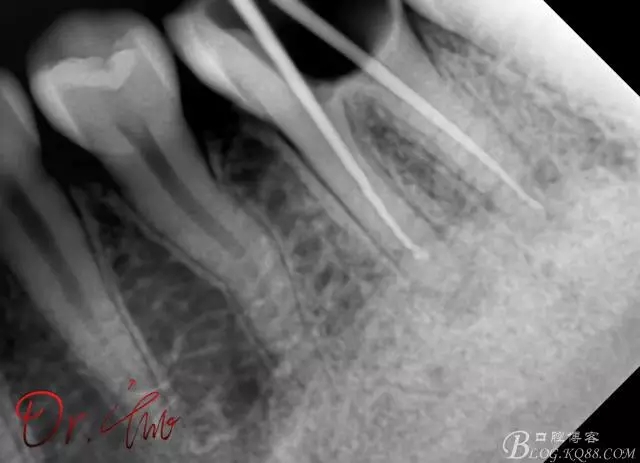

試主尖,在30號02錐度K挫到達根尖后,用02錐度牙膠尖找準位置,進行試尖

640.webp (10).jpg

最后根充,明顯可看到臺階位置,期待預(yù)后效果

640.webp (11).jpg